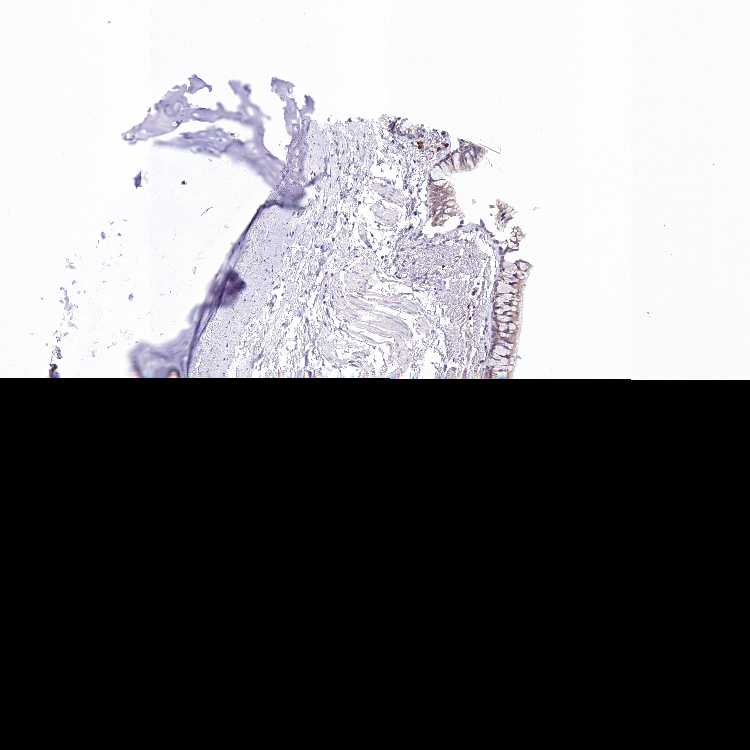

SOFT TISSUE 1 - Antibody stainingi

Antibody staining in the annotated cell types in the current human tissue is reported as not detected, low, medium, or high, based on conventional immunohistochemistry profiling in selected tissues. This score is based on the combination of the staining intensity and fraction of stained cells.

Each image is clickable and will lead to virtual microscopy that enables deeper exploration of all samples and also displays staining intensity scores, fraction scores and subcellular localization as well as patient and tissue information for each sample.

Antibody HPA045089

Fibroblasts Not detected

Peripheral nerve Not detected